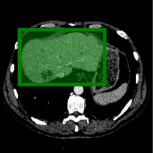

Consider a three-dimensional object within a volume. It is straightforward to produce a 3D bounding box of the object by finding its extreme points in the three coordinate axes. While this 3D bounding box will be tight in the 3D sense, its rectangular cross-sections will not, in general, remain tight with respect to the planar cross-sections of the volume. Fig. 1 illustrates such a case for the task of liver segmentation in a CT volume. In the Experiments section we show that the success of existing 2D weakly-supervised segmentation methods relies on the bounding boxes being tight and therefore the tightness of the individual 2D bounding boxes should be corrected before training and applying a segmentation CNN.

The global bounding box tightness prior mentioned above assumes that each of side of the box is sufficiently close to the target region. This means that for any region shape, each vertical or horizontal line inside the bounding box will cross at least one pixel belonging to the target region. This condition does not hold when the provided annotation comes as a 3D bounding box which is represented as a series of per-slice non-tight 2D bounding boxes. In this case, there will exist vertical or horizontal lines shown as stripes in Fig. 1 (d), that will lie outside of the actual object boundary. In the Experiments section we demonstrate the poor performance of the weakly-supervised approach from [5] when the user-provided bounding box is much wider than the true object of interest.